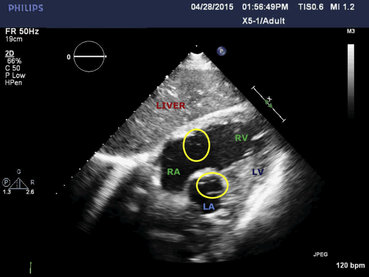

La sintomatologia del paziente è peggiorata rapidamente tanto che hanno provveduto ad un intubazione d'urgenza. Successivamente gli esami hanno mostrato la causa di quel peggioramento critico nelle ecografie e radiografia, sotto.